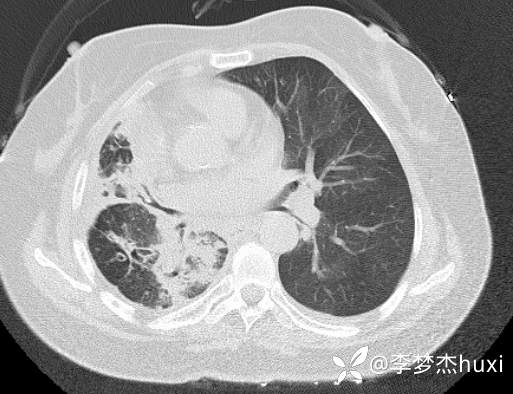

8.22治疗后的胸部CT: